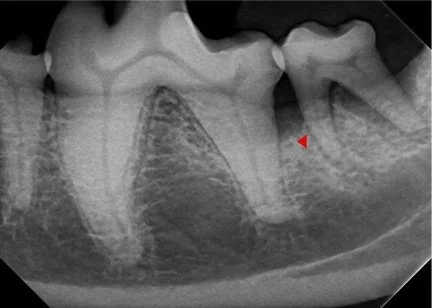

Need some help interpreting your dental radiographs? Full mouth dental radiographs can be submitted for evaluation. A written report on all images will be provided.